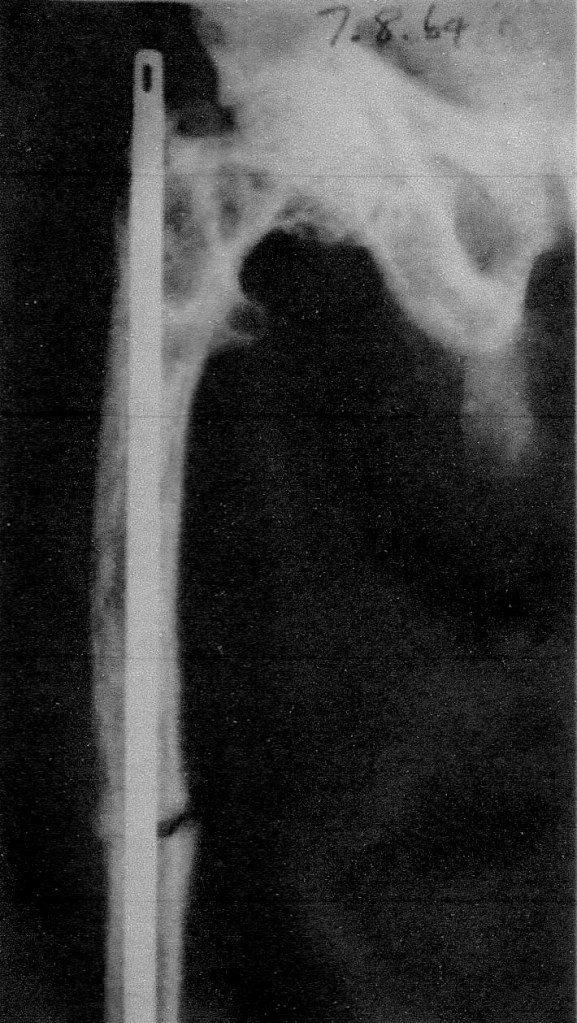

On one notorious occasion Tony was helping his registrar from Canada, a Dr Norm Abel, put an intramedullary Kuntscher-nail (K-nail) in a fractured shaft of femur. I may have been second assistant or even an observer, I cannot remember. All was proceeding reasonably smoothly, albeit with loud animated instructions from Tony, when they struck a problem – a major problem. The nail is long piece of stainless steel, constructed to be hammered down the central shaft of the femur from the hip end when the fractured segments are aligned. Tony had the steel hammer and the nail was about half way down when it became jammed – really jammed. Clearly, they had chosen a nail of too great a diameter to slide down the shaft. Tony’s voice went up an octave and pandemonium reigned.

There is a specially designed extractor hammer which fits into cutout in the top of the nail in order to remove it after the fracture has united. This was called for but despite the efforts of both surgeons the nail was firmly jammed and would not budge. The extractor hammer which slid up a steel shaft was smashed in the process and the procedure descended into chaos. They knew not what to do. Eventually the protruding length of the K-nail was sawn off and the procedure abandoned.

Well, lessons for everybody, myself included. Know how to extract yourself from every possible complication and then some!

Next day on the ward round John Shelswell had the debacle described to him. No problem he declared. ‘Simply make vertical cuts in the femur to allow the shaft to give a little and out the nail would have come!’ ‘Oh,’ said Tony honestly, ‘I didn’t know that!’

Well, despite his shortcomings, and he was rather a joke around Rochford Hospital, we of the resident staff were all beneficiaries of Tony’s teaching. K-nail in situ